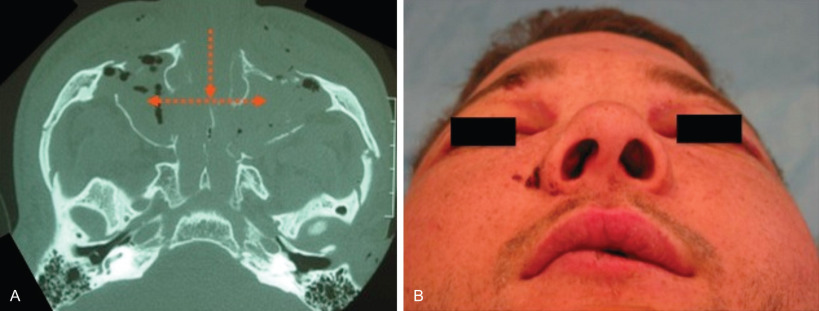

A panfacial craniofacial injury refers to fractures present simultaneously in the cranio-orbital (upper third), orbitozygomaticomaxillary (middle third), as well as the mandibular (lower third) portions of the craniofacial skeleton ( Fig. 1.19.1 ). This requirement of panfacial injuries to have fractures present in all three levels of the face is not consistently used among trauma studies, with some authors including patients with severe injury in only two levels. The incidence of panfacial injury ranges from 0.8% to 3% in large craniofacial fracture series, and can occur from a number of mechanisms, including blunt, penetrating, and avulsive mechanisms in all age groups. These injuries present challenges in surgical management to avoid long-term sequelae of inadequate correction, including increased facial width, enophthalmos, facial retrusion, and malocclusion ( Figs. 1.19.2 and 1.19.3 ). The purpose of this chapter is to provide an algorithm for management of these panfacial injuries in order to optimize outcomes.